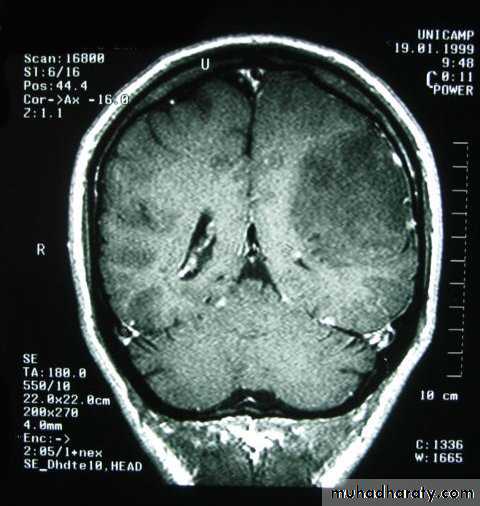

Metastatic Brain TumoursMRI